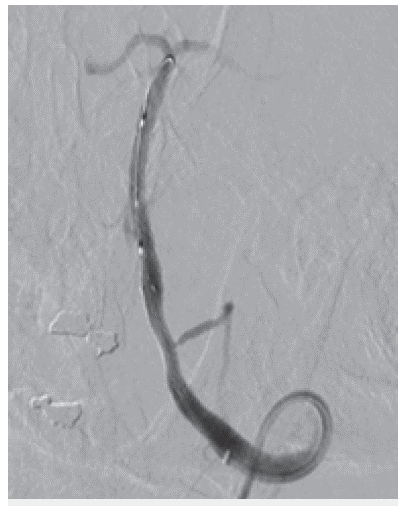

Liberación controlada de stent coronario balón expandible

Figura 3: Liberación controlada de stent coronario balón expandible